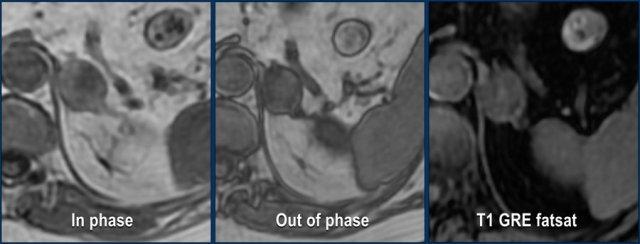

MRI được thực hiện cho tổn thương tình cờ tuyến thượng thận trái phát hiện trên CT không tiêm thuốc và pha động mạch ở bệnh nhân nam 61 tuổi có phình động mạch chủ bụng.

Trên CT không tiêm thuốc, tỷ trọng là 18 HU.

Ảnh T1 đảo pha cho thấy sự giảm tín hiệu không đồng nhất kín đáo so với ảnh đồng pha.

Lưu ý rằng chuỗi xung T1 có xóa mỡ không có giá trị trong việc phát hiện mỡ nội bào vi thể.